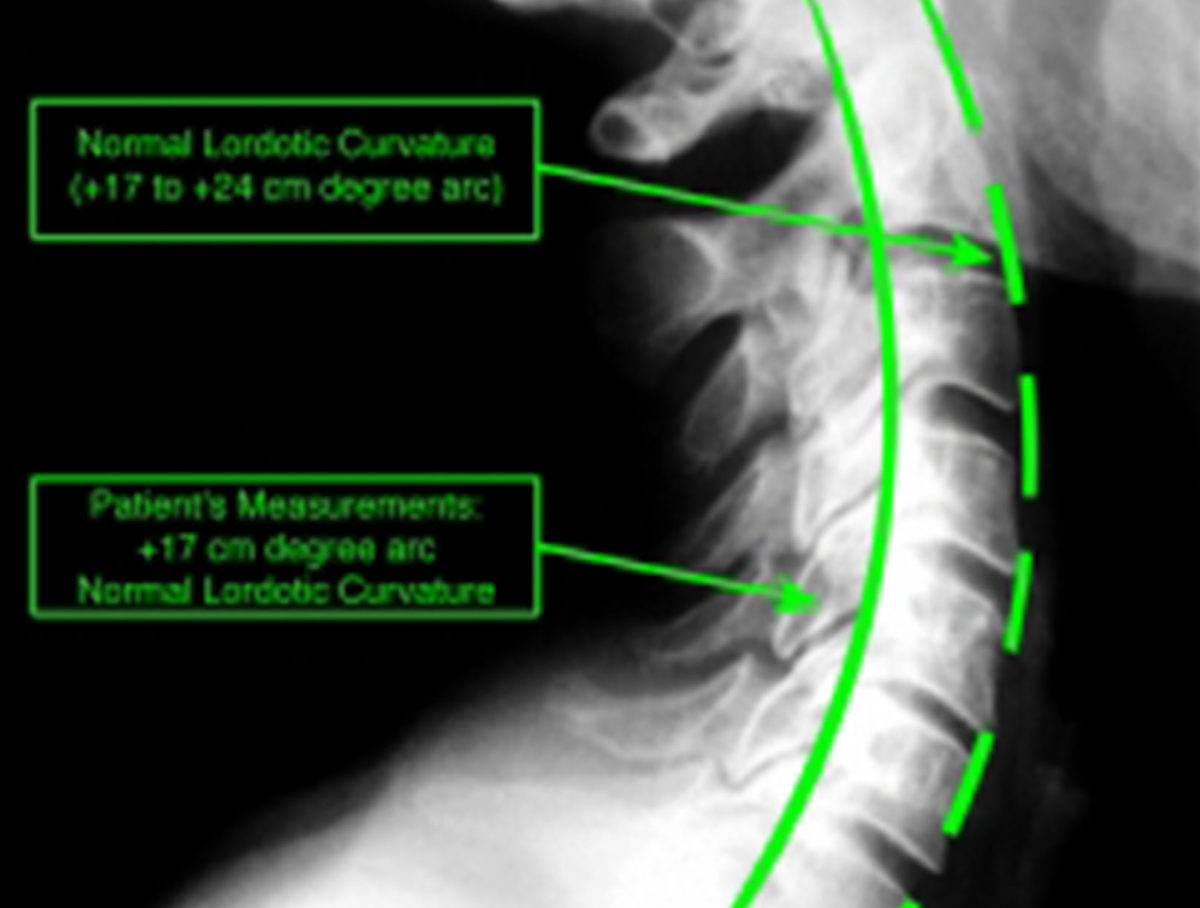

Tag neck curve Chiropractor Auburn Hills, MI 48326 Upper Cervical Care Curved Neck Xray military neck is an unusual curve in your cervical spine (this is your neck) called cervical kyphosis. kyphosis is curvature of the spine that causes the top of the back to appear more rounded than normal. military neck, or cervical kyphosis, is a rare condition that involves an abnormal curvature of the cervical spine, or neck. . Curved Neck Xray.

Why We Take Spinal XRays Align Corrective Chiropractic Curved Neck Xray military neck, or cervical kyphosis, is a rare condition that involves an abnormal curvature of the cervical spine, or neck. cervical kyphosis, or military neck, occurs when your cervical spine is straight or curves toward your front. military neck is an unusual curve in your cervical spine (this is your neck) called cervical kyphosis. kyphosis, an. Curved Neck Xray.